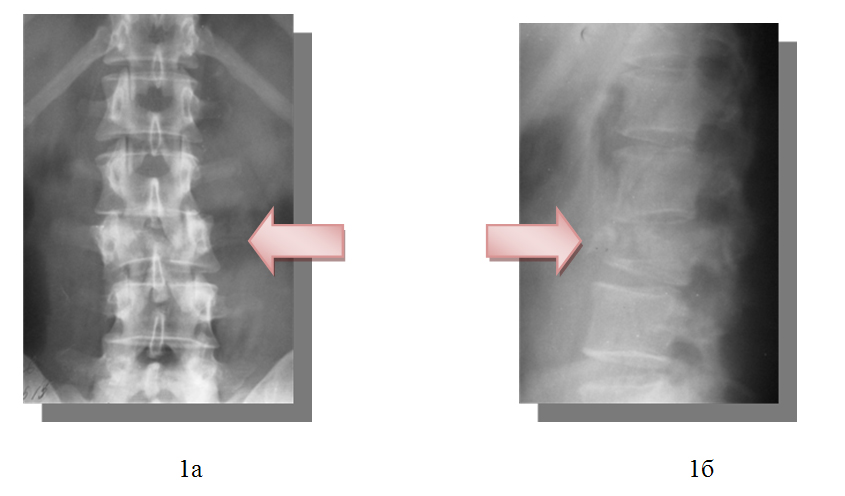

1) закрытый нестабильный, компрессионно-оскольчатый перелом тела и левого поперечного отростка 3 поясничного позвонка, перелом дуг 3-4 поясничных позвонков и субкомпенсированный стеноз позвоночного канала на уровне 3 поясничного позвонка, радикулопатия 4 поясничного корешка слева, посттравматическая кифотическая деформация позвоночника.

2) закрытый винтообразный перелом нижней трети левой большеберцовой и малоберцовой костей со смещением отломков.